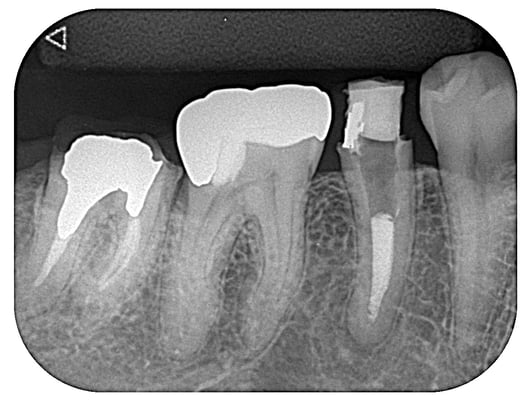

右上7番

根管内には、3本の破折ファイルの残存。それ以外は、多量の軟化象牙質(一部は髄床底穿孔)。根尖病巣の存在。対合歯とのクリアランス少なく、保存するにも補綴するには無理か?と思われましたが、約1年。月に1度。当院から片道2時間半、かけて通っていただき、無事に補綴に至りました。

これから矯正治療になりますので、まだまだ長い道のりです。